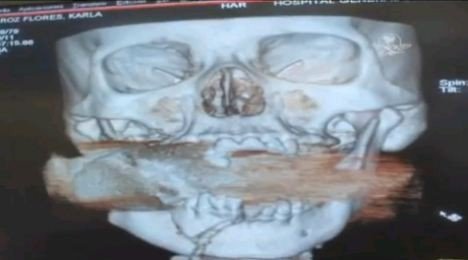

環球網訊 墨西哥一名被稱之為“奇跡女”的女子剛剛經歷了一場不可思議的驚險。她在街上賣海鮮時被一顆剛剛發射的手榴彈擊中,未爆炸的手榴彈正好嵌入她上下頜骨之間。墨西哥軍方防爆專家及5名醫生在一片空曠的田野里為她進行手術,從她臉上取出了這顆隨時可能爆炸的手榴彈。

英國《每日郵報》9月有28日報道稱,育有三子的卡拉弗洛里斯生活在墨西哥錫那羅亞州的庫利亞坎。一天,正在街上販賣海鮮的她在聽到一聲巨響后,被一件物體擊倒。她感到臉上一陣熱,伸手摸到一灘血。隨即失去知覺的卡拉被送往醫院,醫生在為她進行X光掃描時發現,一顆未爆炸的手榴彈卡在卡拉的上頜骨與下頜骨之間。

醫院立刻提高了警覺。顯然,這個手榴彈在被手榴彈發射器發射后沒有爆炸,卻嵌入了卡拉頜骨正中。由于它隨時有爆炸危險,卡拉被隔離開來,醫院的病人及員工都被撤離。由于醫生都不愿意為卡拉動手術,最后醫院院長自愿來完成這個驚心動魄的手術,另外兩位麻醉師、一位醫生及一位護士為其充當助手。

當天深夜,在兩名墨西哥軍方防爆專家的護送下,醫生們將卡拉到了一片空曠的田野中,連夜進行手術。四小時后,醫生終于取出了卡在卡拉頜骨里的手榴彈,而卡拉失去了一半牙齒,整個臉頰都被撕裂,但保住了性命。醫生稱,她在未來三年都將接受整形手術。